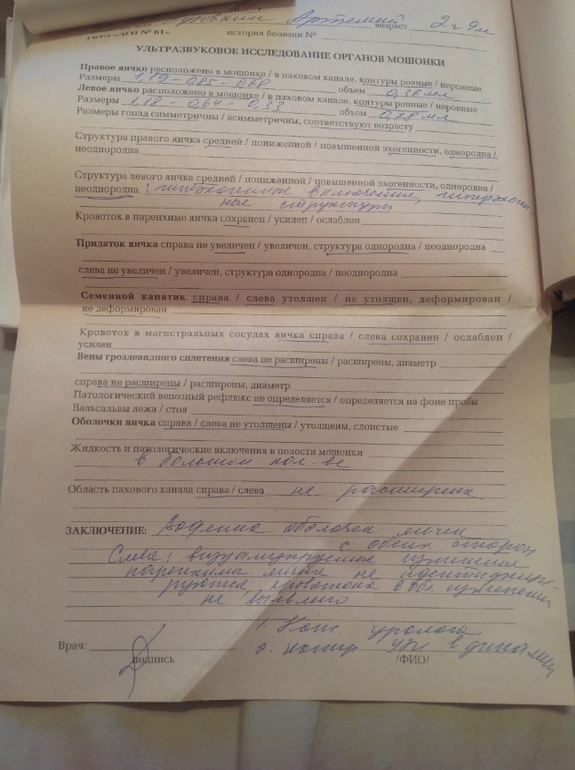

Здравствуйте Максим Викторович! Подскажите, пожалуйста! У сына с рождения водянка, хирург говорил, что можно подождать до 3 лет. Сейчас ему 2г9мес. Сегодня сделали узи. Помимо водянки на левом яичке гипоэхогенные включения и гипоэхогенная структура. Что это и чем это грозит? Нас направили к урологу, но попадём к нему только на следующей неделе. Сейчас всякие разные мысли плохие лезут в голову. И стоит ли оперировать данную водянку? Хирург говорил, что если там жидкости очень мало, то не стоит ничего делать. А мало это сколько?

Это так называемый синдром "звездного неба" или синдром "гиперэхогенных включений" в яичке. Что бы сказать что то конкретное, мне надо бы вас смотреть самому и на УЗИ аппарате экспертного класса. Это может и ни о чем не говорить, а может свидетельствовать о наличии проблемы, нужна качественная оценка ситуации и не только по УЗИ